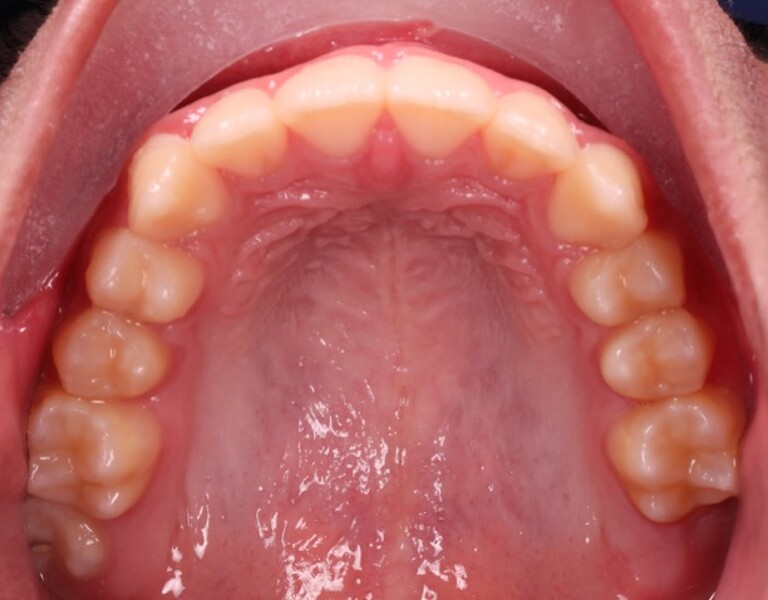

Figs. 2a–e: Pretreatment intra-oral photographs.

Fig. 2b

Fig. 2c

Fig. 2d

Fig. 2e

a narrow, collapsed V-shaped maxillary arch with a 2.0 mm midline deviation to the right.

Cephalometric analysis confirmed a Class II skeletal pattern primarily caused by mandibular retrusion (ANB = 5°; SNB = 69°) and showed reduced mandibular length (94 mm versus a norm of approximately 110 mm; Fig. 4; Table 1). The vertical pattern was normo-divergent (SN/GoGn = 34°). Dentoalveolar analysis showed severe maxillary incisor proclination, pronounced crowding in both arches and an accentuated curve of Spee. Soft tissue analysis showed lower lip entrapment associated with the increased overjet, contributing to an unfavourable facial profile.